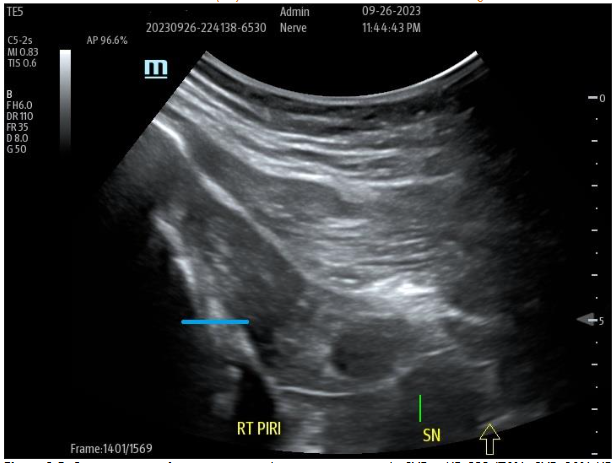

Many examples of important epineural-dissections and fascial inflammatory conditions have been improved with applications of a biocellular mixture, including use of PPP products are becoming a very common, safe and effective protocols. Often by “resting” simulated, entrapped or irritated peripheral sensory nerves, long-term relief is attained. This is considered partially due to fibrin conversion which may provide addition protection while reducing the nerve axonal irritation. This has become a more effective and commonplace option, particularly in areas such as inflamed fascia as in the thoraco-lumbar fascial (TLF), Piriformis/Sciatic areas, and Ilio-Tibial Band (ITB). The PPP or biocellular elements are also capable of providing soothing impacts of the area, plus helping limit inflammatory response and promote recovery. It may be a combination of the anti-inflammatory action of the stem/stromal cells and the fibrinogen contained to form a fibrin protection of irritated nerve structures often missed in regenerative efforts and not available in invasive surgical procedures.

Figure 9A: Pre-Treatment U/S of degenerative Piriformis (sciatic radicular symptoms) no history of trauma, degenerative Pattern within Piriformis musculature with loss of muscle echotexture. Figure 9B: Post-treatment of site at nine months post-treatment with tSVF + HD PRP (70% tSVF: 30% HD PRP (6X – concentration HD PRP) with return of improved muscular echotexture and elimination of radicular sciatic symptoms.